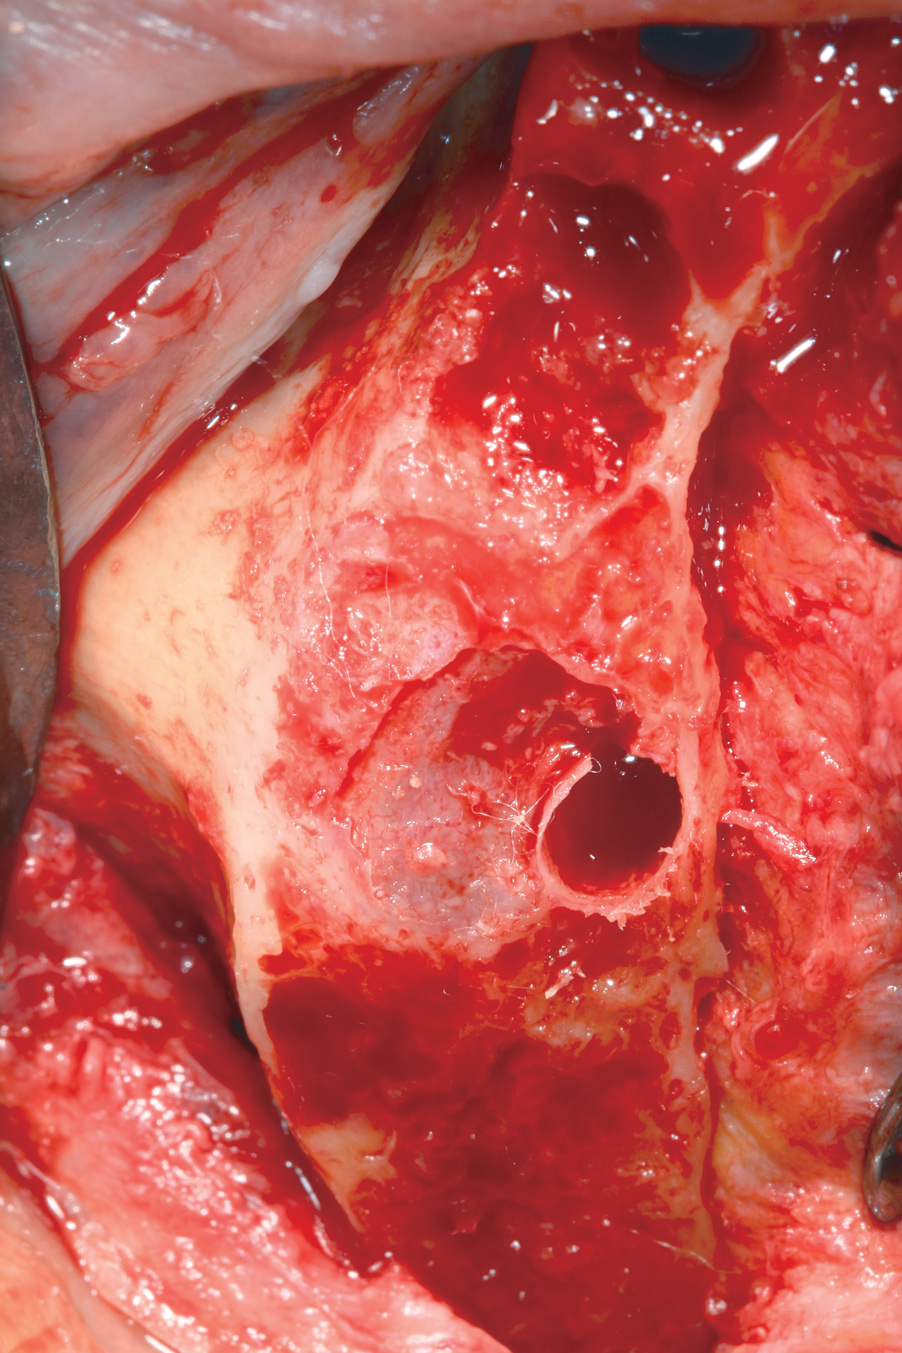

Fig 5. Crestal exposure of the Schneiderian membrane at the initiation of horizontal plane bone reduction.

Figure 5

Fig 6. Curette used to elevate Schneiderian membrane from residual crest to allow for additional horizontal plane bone reduction.

Figure 6

Fig 7. Maxillary arch from Figure 5 and Figure 6 following crestal Schneiderian membrane elevation, horizontal plane bone reduction, and dental implant placement.

Figure 7

Fig 8. Postsurgical panoramic radiograph of patient shown in Figure 5 through Figure 7.

Figure 8

To overcome this complication, the author carefully reduces the residual maxillary crestal bone until crestal exposure of the Schneiderian membrane is achieved (Figure 5). On crestal visualization of the Schneiderian membrane, the author uses curettes to lift the membrane apically from the anticipated plane of bone reduction (Figure 6). The maxillary bone is then reduced apically, and the process is repeated until the desired amount of bone reduction is achieved. When performed in this manner, the Schneiderian membrane remains intact while crestal areas of reduced maxillary bone will have openings of varying degrees depending on the amount of bone reduction (Figure 7). The author does not augment these openings with bone graft and simply closes the surgical site with primary closures of thick mucogingival flaps. To date, patients receiving treatment from the author in this fashion have had no adverse outcomes (Figure 8).